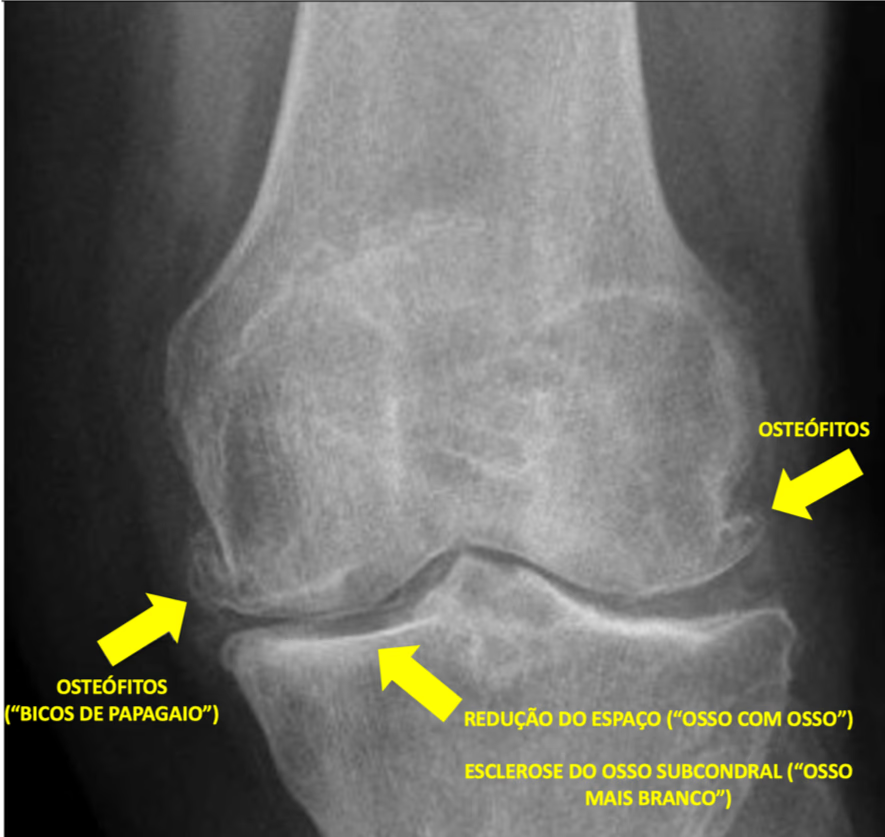

- Radiografias: são essenciais para visualizar alterações estruturais nas articulações, como a redução do espaço articular e a presença de osteófitos.

- Formação de osteófitos: também conhecidos como esporões, os osteófitos são crescimentos ósseos que se formam nas bordas das articulações, podendo ocasionar dor e rigidez.

- Mudanças na estrutura óssea: o osso abaixo da cartilagem pode endurecer e formar cistos, resultando em desconforto e dor.